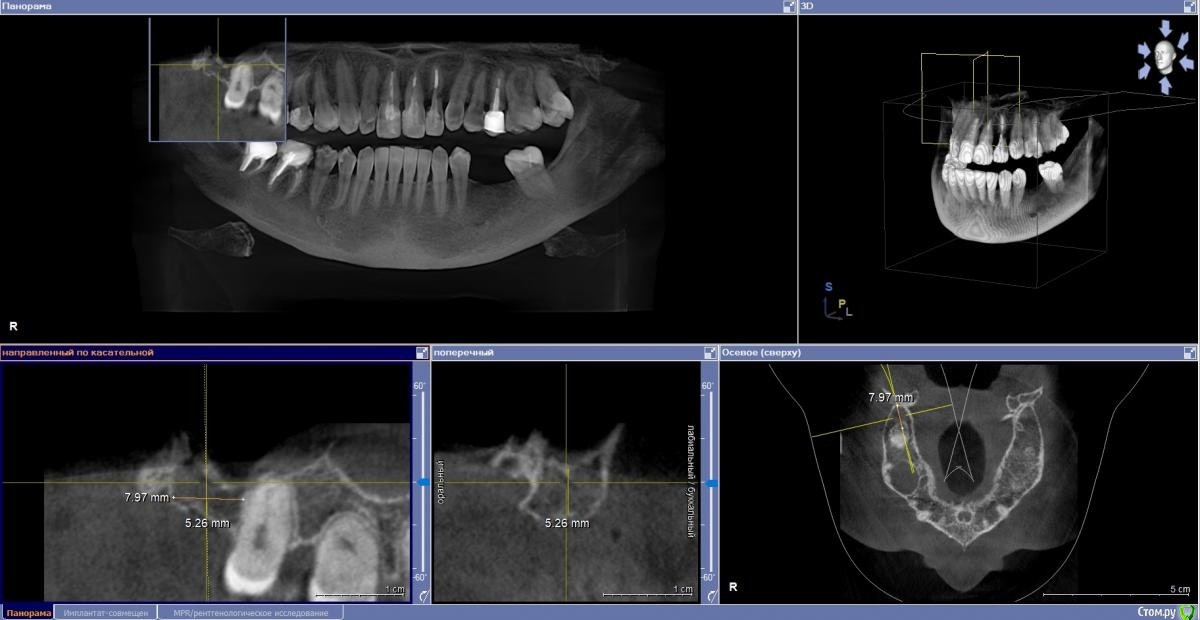

Fin Опубликовано 4 ноября, 2020 Поделиться Опубликовано 4 ноября, 2020 (изменено) Здравствуйте коллеги. В клинику обратилась пациентка с жалобой на эстетику передних зубов. В ходе осмотра и составления плана на КТ обнаружилась резка корня 22. Перфорация вестибулярной стенки на КТ не наблюдается. Думаю что при полном удалении корня вестибулярная стенка тоже уйдет. Техника IDR и B2S невозможна т.к. присутствуют восьмые зубы.Как вы считаете, стоит ли попытка сделать одномоментную имплантацию с техникой вариантов корневого щита или все таки идти на полное удаление? Изменено 4 ноября, 2020 пользователем Fin Ссылка на комментарий

Fin Опубликовано 5 ноября, 2020 Автор Поделиться Опубликовано 5 ноября, 2020 зависит от ваших мануальных навыковкроме техник IDR и щита есть и классические вполне рабочие методикизапланируйте щит, если не получится будьте готовы сделать имплантацию + алло или ксено графт сст даже при наличии 8 можно забрать Есть восьмёрки - разве это противопоказание к idr? Это показание к удалению 8х)Почему то не получилось приложить скрины в первом сообщении. Мне кажется в области 8го зуба забирать нечего за ним уже как то далековато. Как Вы считаете? Ссылка на комментарий

Дмитрий М Опубликовано 8 ноября, 2020 Поделиться Опубликовано 8 ноября, 2020 судя по снимку щит не получится, по причине его отсутствия 1 Ссылка на комментарий

Fin Опубликовано 9 ноября, 2020 Автор Поделиться Опубликовано 9 ноября, 2020 судя по снимку щит не получится, по причине его отсутствия Благодарю за ответ. Будем делать классику. А я думал наоборот пол дела сделано)) Х. Глюкман говорил что лучше немного подпилить корень в глубину, что бы не прорезался. Хотя тут не два мм а 4. Ссылка на комментарий